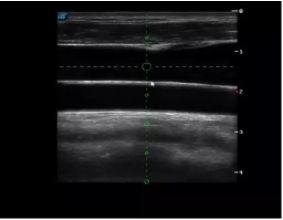

多數(shù)的生殖科醫(yī)生對(duì)于受精卵的植入采用憑經(jīng)驗(yàn)操作或是使用傳統(tǒng)腔內(nèi)探頭引導(dǎo),同樣存在手術(shù)空間小、受精卵放置位置不確定等風(fēng)險(xiǎn)。專業(yè)的宮腔專用探頭,配合專用的窺器使用,為醫(yī)生提供最大的手術(shù)視野。

胎移植臨床圖